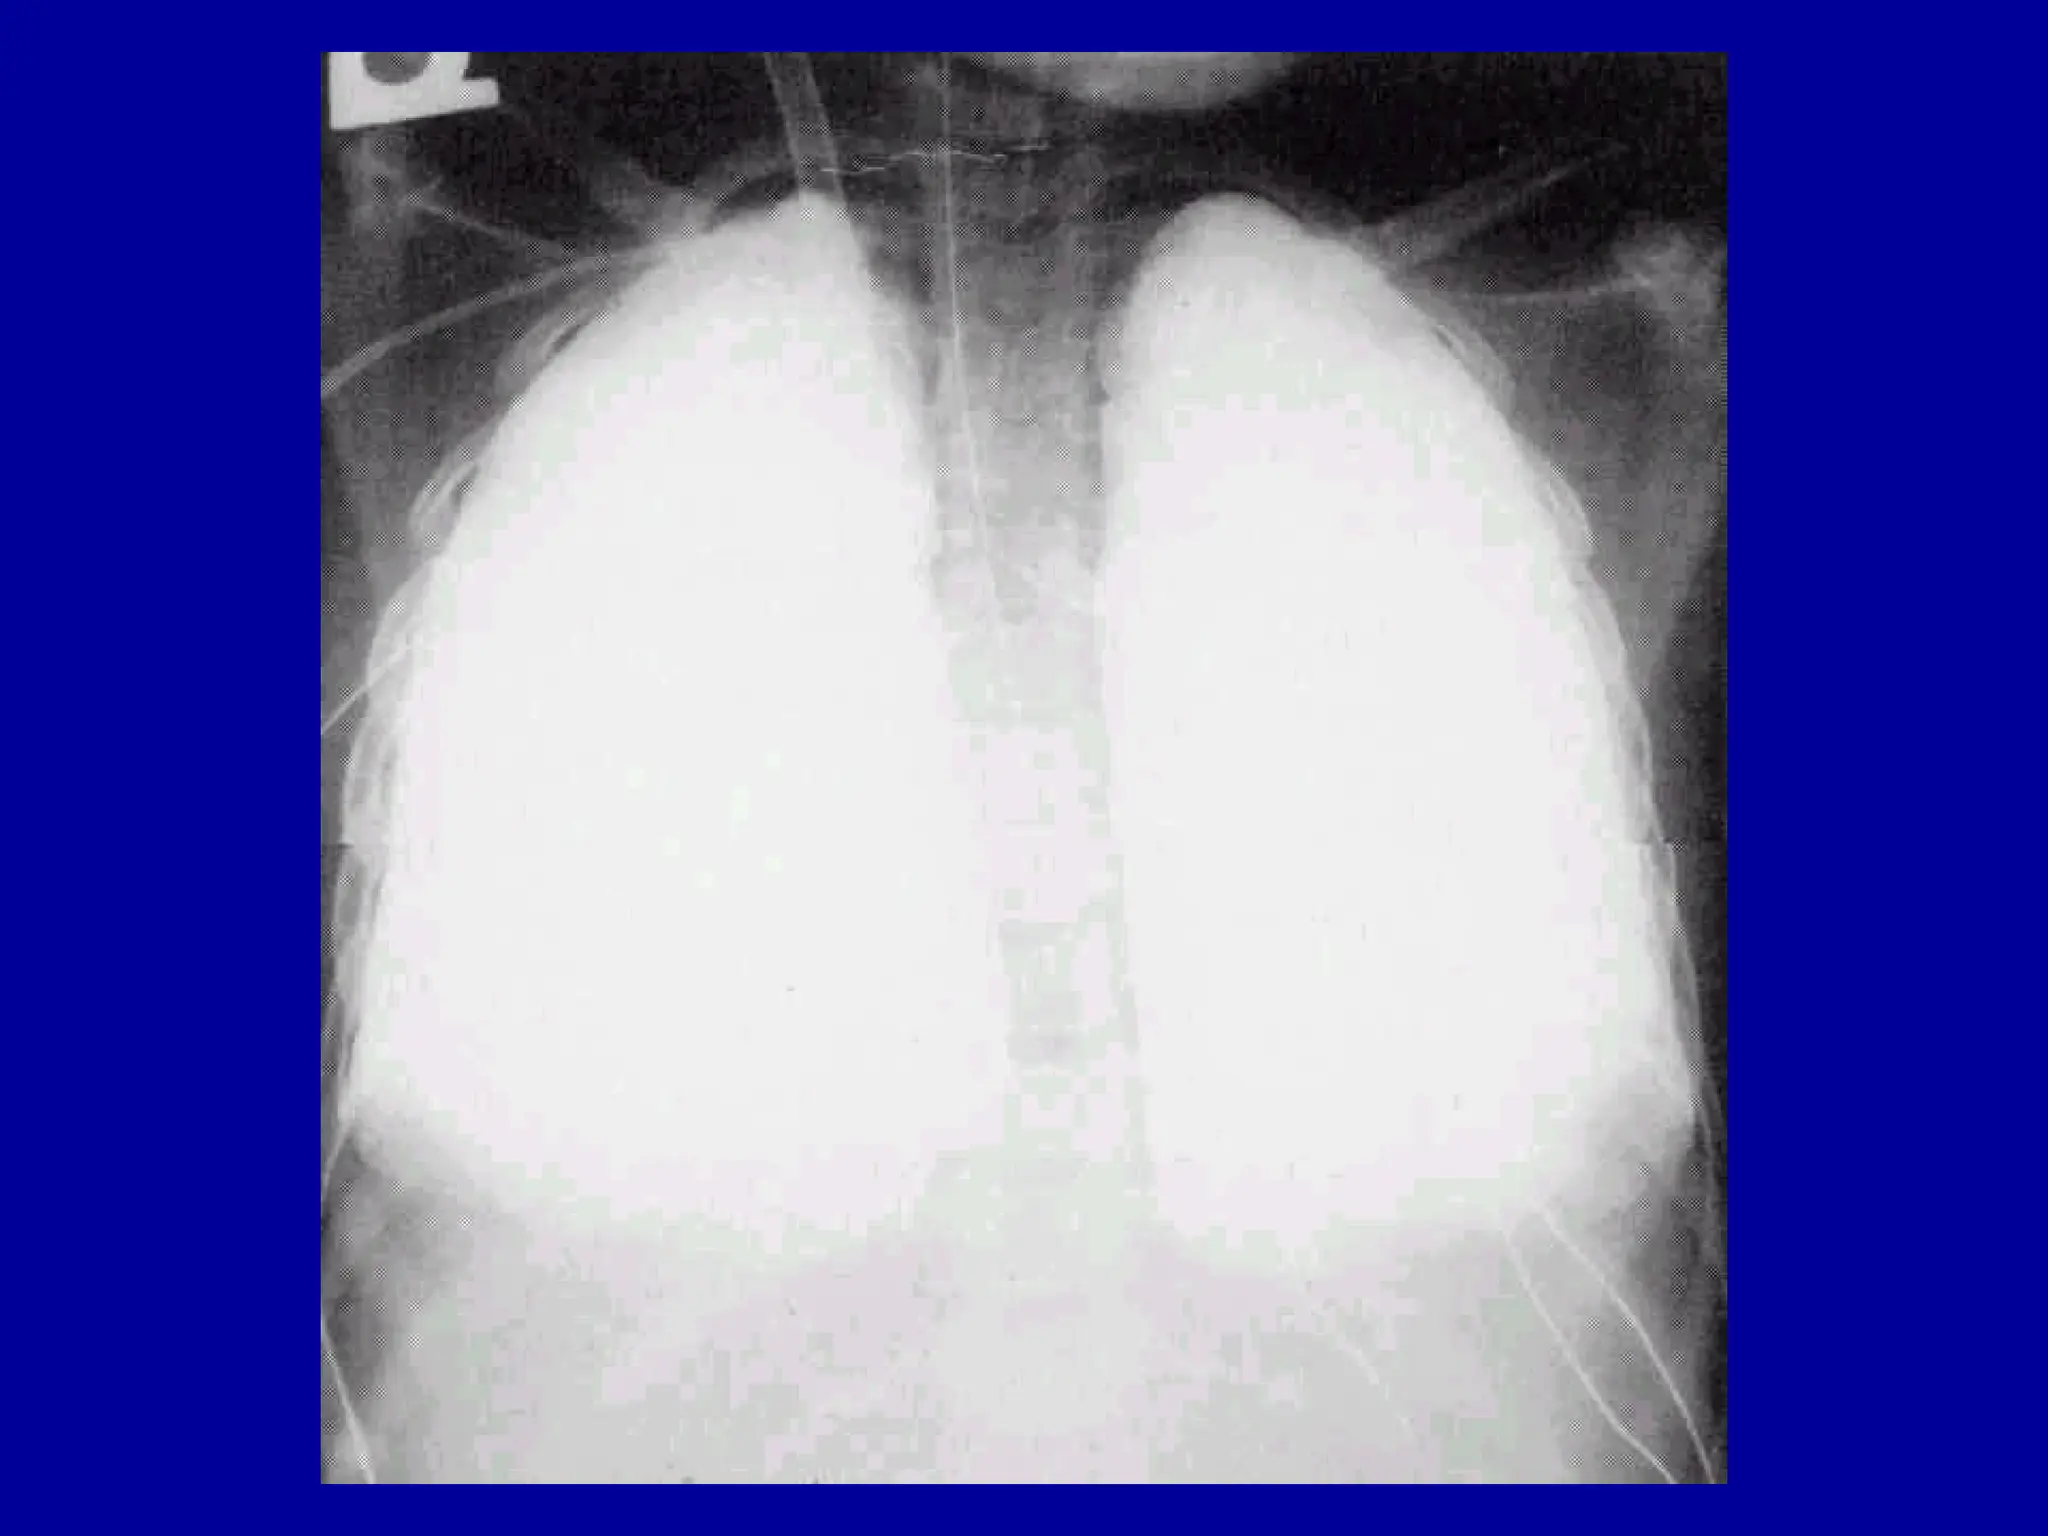

ARDS

(Bilateral

Infiltrates)